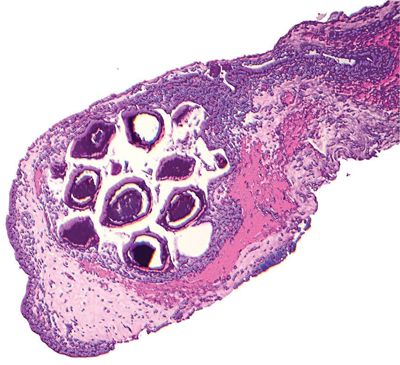

A 60-year-old white Caucasian male, with a history of acne, presented with slate grey pigmentation of his upper forehead, pre-auricular skin, peri-oral area, forearms and shins. The conjunctivae showed bilateral lower tarsal conjunctival multiple black dots. One of these dots was sampled (see Figure 1).

Figure 1.

2. This shows black / brown concretions

in cysts.

4. These are minocycline pigmented concretions. This drug is well recognised to cause pigmentation of sun-exposed skin (increased melanin production) and cause pigmented concretions (iron and drug metabolites, not melanin). Many drugs are associated with conjunctival ‘pigmentation’ of which another example is chlorpromazine.